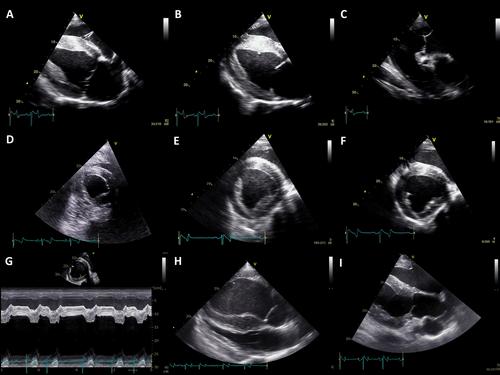

Nine standard echocardiographic recordings were analyzed by experienced (n = 4) and inexperienced (n = 5) observers. RH size, RH function, pulmonary artery (PA) size and distensibility, and the presence of PHT were subjectively assessed as normal, mildly, moderately, or severely changed. Inter- and intra-rater agreement was calculated using percentual agreement (% agree) and kappa (k). Sensitivity and specificity to detect PHT were calculated.